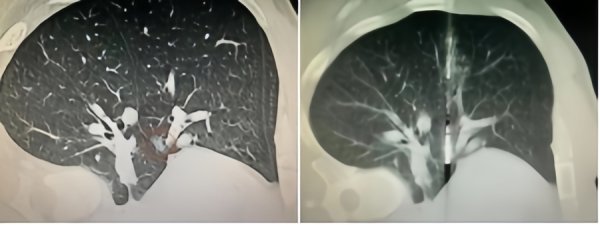

体检发现肺磨玻璃结节,是否只能被动随访或承受开胸手术?上海市东方医院微创介入中心通过大量成功案例给出答案——通过一根仅1.3毫米的微波针,在CT导航下精准消融高....

体检发现肺磨玻璃结节,是否只能被动随访或承受开胸手术? 这个问题,困扰了很多人。上海市东方医院微创介入中心的回答是:当然不是!通过一根仅1.3毫米的微波针,在C....